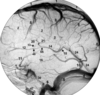

No 19 - 45

19 anterior communicating artery

20 proximal A2 segment anterior cerebral artery

21 callosomarginal branch of anterior cerebral artery

28 pericallosal branch of anterior cerebral artery

31 M1 segment of middle cerebral artery

32 lateral lenticulostriate arteries

33 bifurcation/trifurcation of middle cerebral artery

34 anterior temporal lobe branches of middle cerebral

artery

43 sylvian point

44 opercular branches of middle cerebral artery

45 sylvian(insular) branches of middle cerebral artery